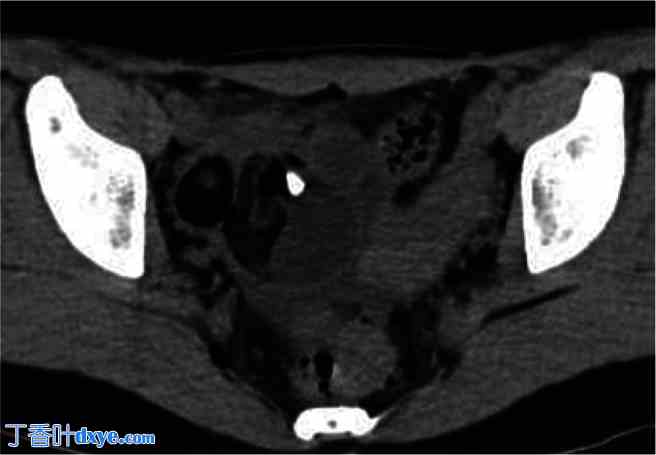

图 2.

CT 扫描显示的右侧卵巢畸胎瘤。

术前平扫CT示右侧卵巢畸胎瘤长5 cm,内含脂肪及钙化部分,该畸胎瘤一年前长3 cm,如图1所示。